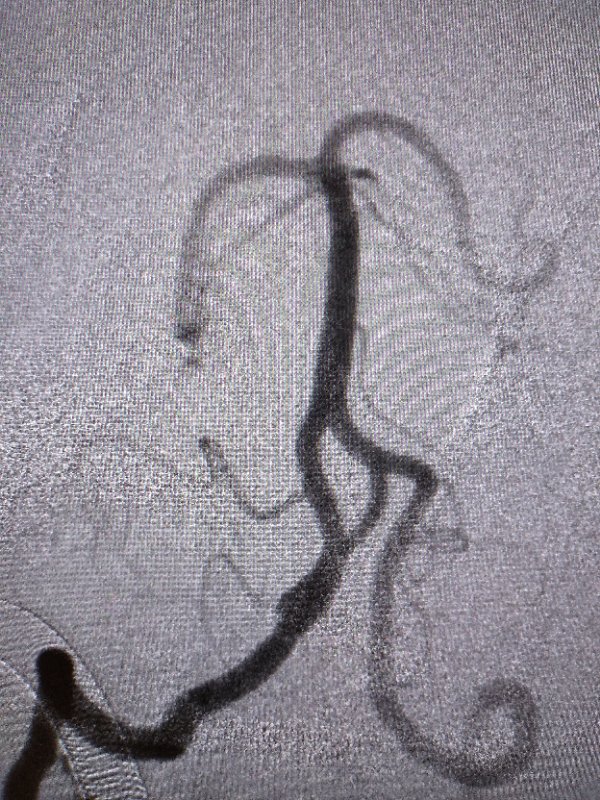

近日,平昌县人民医院神经内科收治了一名因“反复头昏头痛 2 年,加重 1 天”入院的 41 岁女性患者。经过头颅MRI和CTA检查确诊为右侧颅内椎动脉夹层动脉瘤(5.3mm*12.6mm)合并开窗畸形。为降低病变扩大和破裂的风险,彻底治愈本病,我院卒中团队决定为患者进行血流导向装置植入术。

手术由海军军医大学附属长海医院神经外科赵开军教授和平昌县人民医院卒中团队的刘军胜和何天称主治医师一起完成,血流导向装置选用上海微创公司的国产血流导向装置 Tubridge。手术人员对动脉瘤的大小、载瘤动脉的直径以及支架预覆盖的长度进行了精准测量后,将大小合适的支架精准释放于预先规划的位置,充分覆盖病变区,载瘤动脉和分支血管均保持通畅,支架打开良好。整个手过程顺利。术后,患者在卒中中心护理团队的护理下,恢复良好。